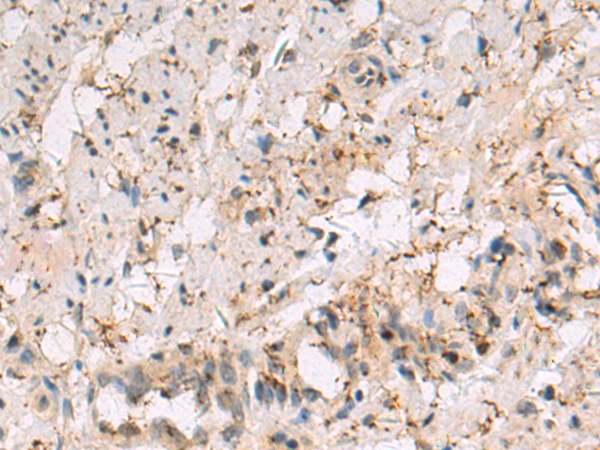

IHC positive control: |

Human breast carcinoma tissue |